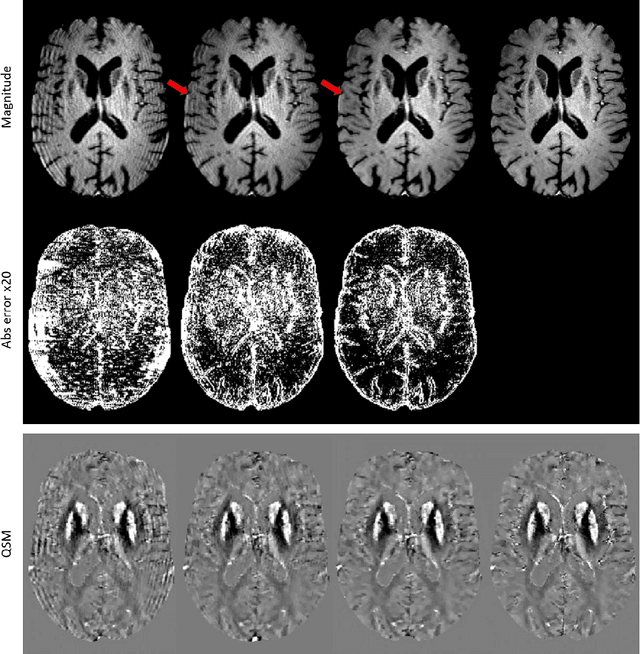

Abstract:An approach to reduce motion artifacts in Quantitative Susceptibility Mapping using deep learning is proposed. We use an affine motion model with randomly created motion profiles to simulate motion-corrupted QSM images. The simulated QSM image is paired with its motion-free reference to train a neural network using supervised learning. The trained network is tested on unseen simulated motion-corrupted QSM images, in healthy volunteers and in Parkinson's disease patients. The results show that motion artifacts, such as ringing and ghosting, were successfully suppressed.